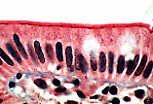

单层柱状被覆上皮(回肠)

单层柱状被覆上皮分布于回肠(小肠的一部分)。

小肠在食糜消化和消化产物营养吸收中发挥关键作用。为实现吸收功能,小肠与食糜接触的表面积通过多种结构被显著扩大:小肠的长度(肠袢)、黏膜皱襞、肠绒毛和微绒毛。 |

肠绒毛表面覆盖着肠上皮,包含两种细胞:吸收细胞(纹状缘细胞)和杯状细胞。 |

肠绒毛由中央结缔组织轴心和表面覆盖的肠上皮构成。绒毛之间可见 利贝昆氏腺(肠腺) 的开口。 |

肠上皮通过基膜与下方的结缔组织相连。细胞的基底面贴附于基膜,游离面朝向肠腔。细胞核呈单层排列于高柱状细胞的下1/3处。这一形态学特征表明肠上皮属于单层柱状被覆上皮。 |

肠上皮细胞的形态特征与其功能特化相适应。

吸收细胞为高柱状细胞,卵圆形细胞核位于基底部,游离面有一粉红色区域即纹状缘,其下方有一条嗜酸性红线。透射电镜显示,纹状缘由微绒毛构成,为吸收细胞提供了巨大的游离面以吸收营养物质;而嗜酸性红线对应终末网——这是一种细胞质区域,微绒毛内的肌动蛋白微丝在此锚定于中间丝。 |